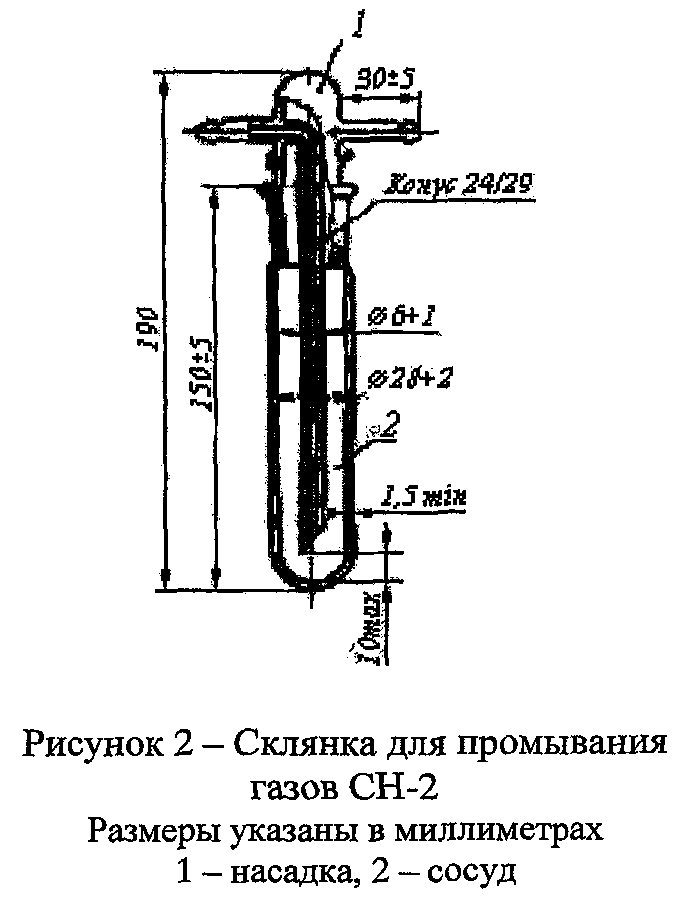

Определение проводят в склянке для промывания газов (рис. 1 или рис. 2).

Перед началом испытания склянку продувают в течение 1-2 мин испытуемым кислородом, который отбирают из баллона через редуктор.

В две одинаковые склянки для промывания газов наливают по 100 мл 5% раствора бария гидроксида (поглотительный раствор).

Испытуемый раствор. Через раствор в одной из склянок пропускают 1000  кислорода в течение 15-20 мин.

Объём кислорода, пропущенный через поглотительный раствор, измеряют с помощью склянки с тубусом (рис. 3) или прибора для отбора проб газа (рис. 4), присоединенного к короткой трубке склянки (рис. 1 или 2) на выходе газа.